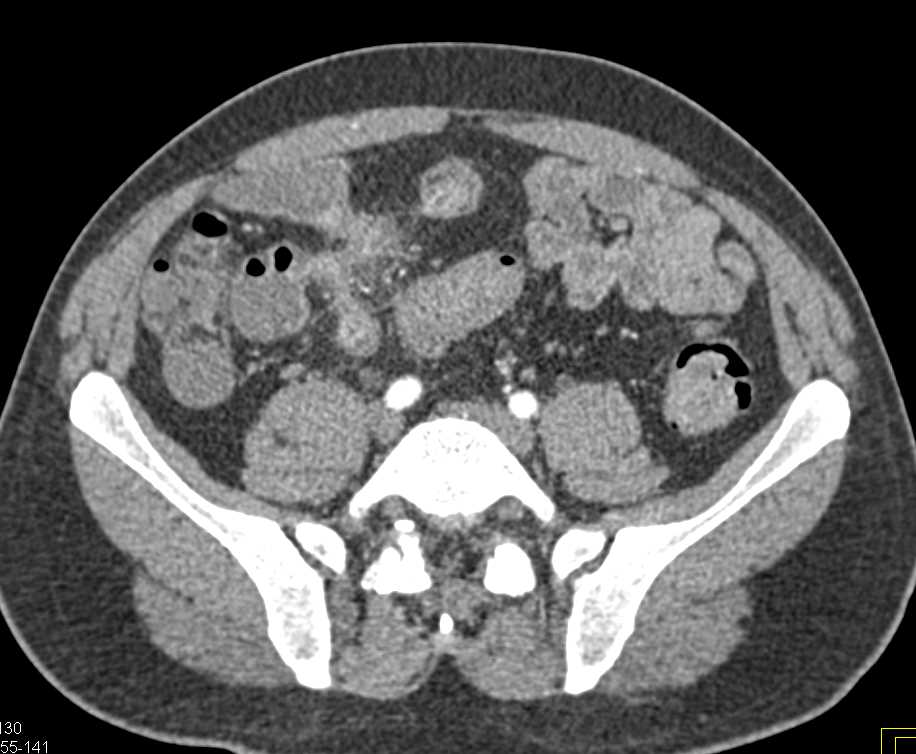

Crohn's Disease with Enetero-Enteric Fistulae